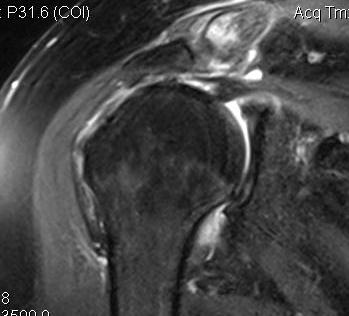

Hoffa fracture

Definition

Coronal plane fracture of distal femoral condyle

- intra-articular

- often only attachment is posterior capsule

Xray

Coronal plane fracture of distal femoral condyle

- intra-articular

- often only attachment is posterior capsule